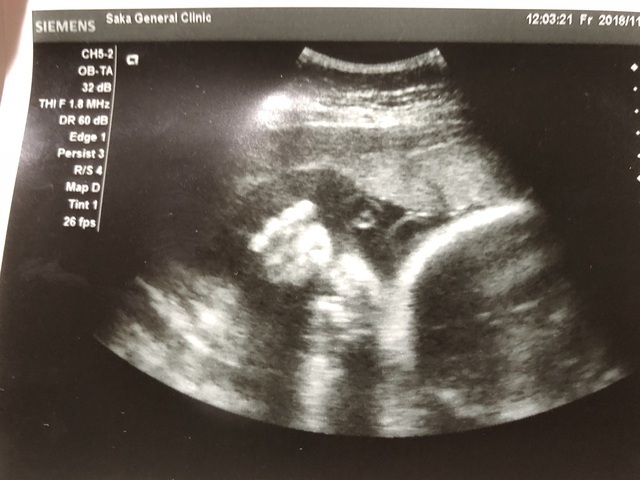

37週5日(37w5d・女の子)|ココちゃんママ さん(26歳)

エコー写真撮影時のエピソード:

いつも通りにエコーをしていたらなんとあっかんべーをしていました!いつもは笑ったりすることのない診察室に私と主人、お医者さんの笑い声が溢れました。

見た瞬間、みんなは驚きとともに大爆笑でした!お医者さんにとっても珍しかったようで顔だけアップにしてじっくり見ていました。